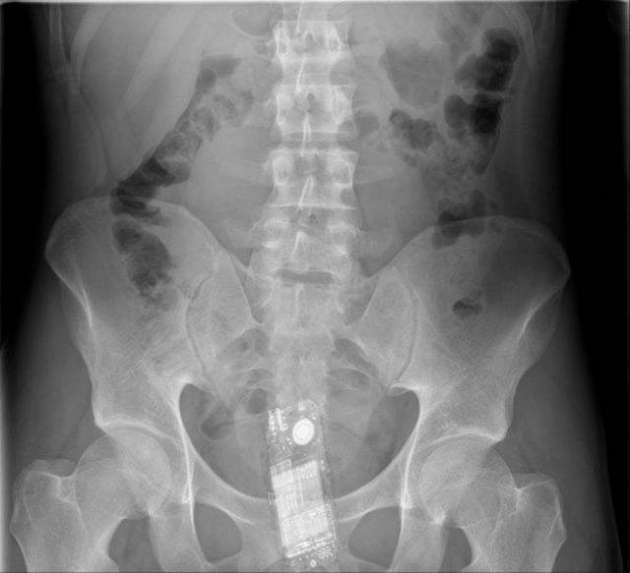

İÇİNDEKİ ŞEYE RÖNTGEN UZMANLARI ŞOK OLDU!

RÖNTGEN UZMANLARI ŞOK OLDU!

,Dünyada çekilen bu röntgenler hem röntgen uzmanlarını hemde görenleri şok ediyor...